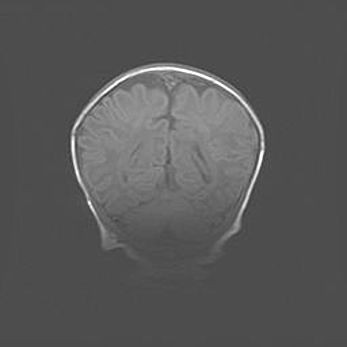

Наружная гидроцефалия с возможной атрофией височных областей.

Возраст: 28 дней

Вес: 3670 г

Пол: мужской

Окружность головы: 38 см

Срок гестации: 40 недель

Гидроцефалия головного мозга у новорожденных – это заболевание, которое характеризуется скоплением избыточного количества спинномозговой жидкости в желудочковой системе головного мозга в результате затруднения её перемещения от места выработки к месту поглощения в кровеносную систему или вследствие нарушения абсорбции. При открытой наружной форме гидроцефалии у новорожденных расширяются и переполняются субарахноидные пространства.

При нормотензивных  формах,  которые,  как  правило,  являются  следствием  перенесенных ишемических  повреждений  паренхимы  мозга,  возможно  сочетание микроцефалии  с нормотензивной гидроцефалией. В основе данных изменений лежит атрофия больших полушарий с преимущественной  локализацией  в  лобно-височных  областях.